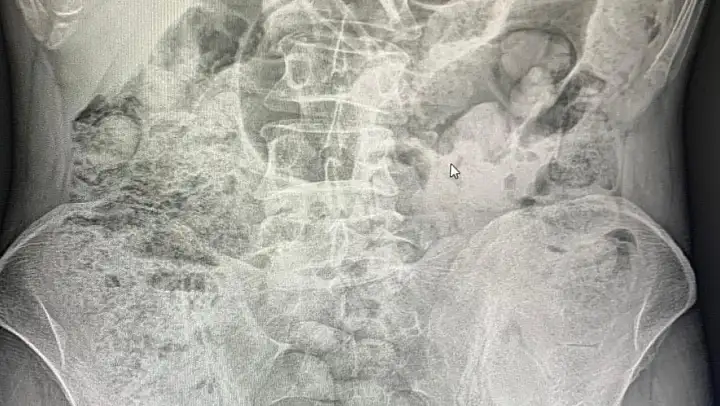

Narkotik ekiplerince yapılan detaylı inceleme ve değerlendirmelerde, şahısların uyuşturucu maddeleri batı illerine sevk etmek amacıyla bedenlerinde, yutma yöntemiyle mide bölgesinde taşıdıkları belirlendi.

Sağlık ekipleri eşliğinde hastaneye sevk edilen şüpheliler, yaklaşık 10 gün süren tıbbi takip ve tedavi sürecinin ardından, cerrahi yöntemler kullanılarak ameliyata alındı. Yapılan operasyonlar sonucunda şüpheli şahısların midelerinden 119 paket halinde toplam 1 kilo 597 gram uyuşturucu madde çıkarıldı.